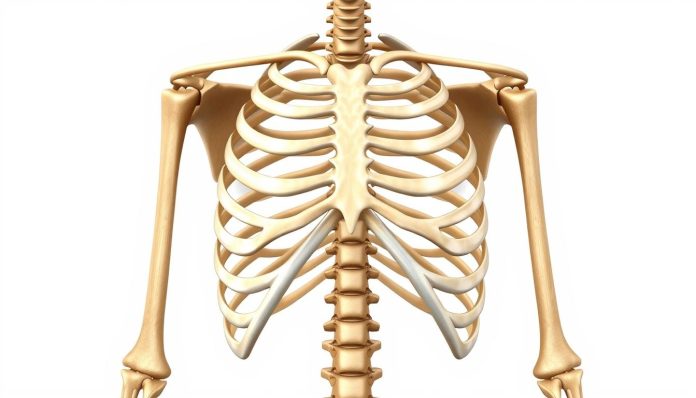

القفص الصدري هو هيكل عظمي مهم يحمي الأعضاء مثل القلب والرئتين. يحتوي على 12 زوجًا من الأضلاع على جانبي الصدر. هذه الأضلاع توفر حماية قوية للجهاز التنفسي والقلبي.

العظام الضلعية مهمة في حماية الأعضاء من الصدمات. كل زوج من الأضلاع يساعد في بناء جدار صدري مرن ومتين. هذا يسمح بحركة التنفس الطبيعية.

عدد وتوزيع الأضلاع في القفص الصدري

الأضلاع الحقيقية والكاذبة

القفص الصدري يتكون من أنواع مختلفة من الأضلاع:

- الأضلاع الحقيقية: السبعة الأزواج الأولى التي ترتبط مباشرة بعظم القص

- الأضلاع الكاذبة: الأزواج من الثامن إلى العاشر وترتبط بشكل غير مباشر

الأضلاع العائمة وخصائصها

الأضلاع العائمة هي الزوجان الأخيران (11 و 12). لا يرتبطان بعظم القص. هذه الأضلاع تتميز بحركة مرونة أكبر، مما قد يسبب متلازمة الضلوع الوهمية.

الفروق التشريحية بين الرجل والمرأة